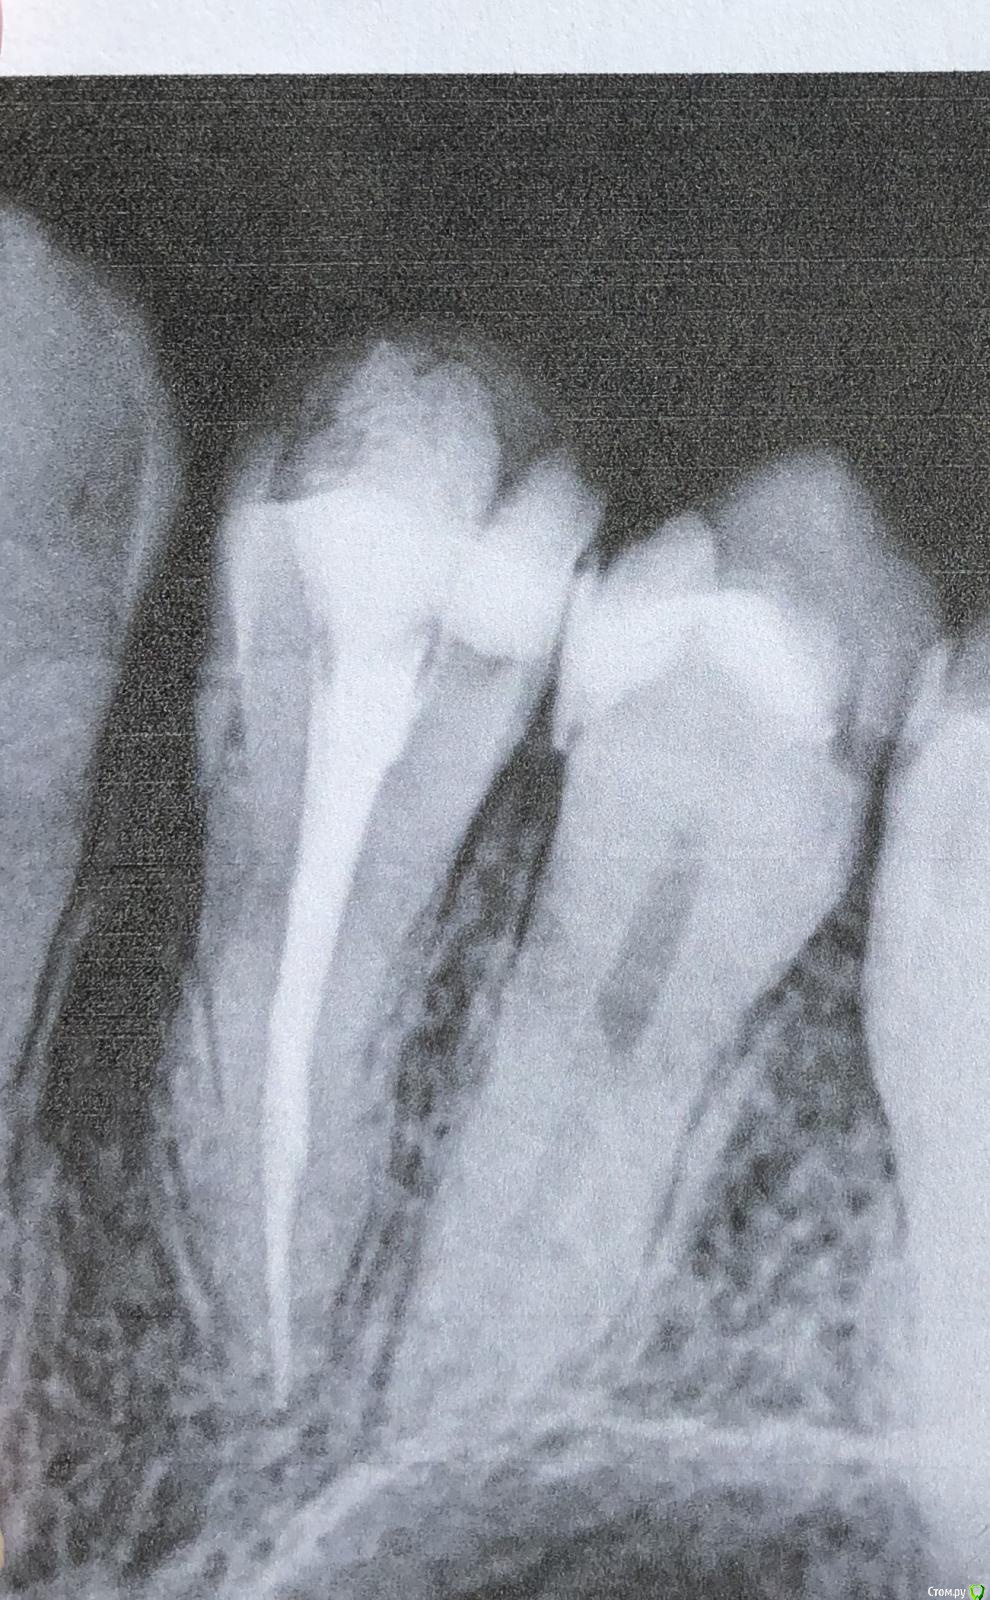

Olga2396 Опубликовано 6 октября, 2019 Поделиться Опубликовано 6 октября, 2019 (изменено) Зуб не болит 4й,но при постукивании чувствителен. Что с боку если постучат, что если постучать на жевательную поверхность.При первом лечении каналов зуб продолжал реагировать на горячее, был крайне чувствителен после горячего,языком было недотронуться. Врач перелечила каналы,боль уменьшилась,при надкусывании не больно, но непонятно почему если постучать неприятно, хотя с другими зубами у которых есть нерв нет неприятного ощущения. + переживаю из за того что выведено за верхушку корня, гуттаперча ли это? Или силлер, пломбировали мне кстати эндометазоном. Надо перелечивать? Или смотреть за состоянием зуба через пол года,будет ли увеличиваться чувствительность или уменьшаться.+ ко всему говорят об удаление нерва из 5го зуба. Зуб чувствителен на холодное,иногда горячее,но не пульсирует,ночных болей нет. Надо ли удалять? Говорят у меня анатомия зубов что нерв близко расположен к поверхности зуба,но при препарировании не была вскрыта пульповая камера и сказали дентин плотный, но 5 зуб чувствителен на холодное,но не больно,обезболивающее не пью и проходит сразу же. Я уже устала с этими зубами, вроде пролечила, а неприятных ощущения есть. 4й зуб пролечен уже как месяц. 5й пока не удаляют нерв смотря за динамикой,есть ли боли нет. Иногда сам как будто микротоком мимолетно стрельнет, ощущения как если бы укололи палец,не больно и пройдётсразу же. Не пульсирующая.1. До удаления нервов 4й5й зуб2. После удаления нерва,первая попытка (боли,чувствительностью горячее)3,4- после 2го лечения в разных боковых проэкциях снимок. Состояния на данный момент 4 и 5 зубаНа 5 снимке красным я отметила потемнее похоже на доп.ветвь канала. На снимках 3,4 есть это ответвление. Это доп. Канал?или особенность снимка? Изменено 6 октября, 2019 пользователем Olga2396 Ссылка на комментарий

red_butler Опубликовано 10 октября, 2019 Поделиться Опубликовано 10 октября, 2019 Четвертый пролечен достойно, дискомфорт при постукивании должен пройти. Зуб обязательно восстановите искусственной коронкой. Пятый, доктор оставил часть старой пломбы? По рентгену необходимости лечения каналов не увидел. По снимку есть вопросы по контактным пунктам между пятым и шестым - пломбировочный материал в межзубном промежутке, на шестом, его нужно убрать. Если боли в пятом быстро проходящие, и не исчезнут, то ставить вопрос о повторном лечении Ссылка на комментарий

Olga2396 Опубликовано 4 ноября, 2019 Автор Поделиться Опубликовано 4 ноября, 2019 Пишу почти через месяц. пломбу переделали, но блин 5й зуб реагируете на холодное все так же, при длительной нагрузке ноет. Где десна воспаляется периодически,зубная нить рвётся.Сказал врач что может отдавать так 4й, мол там корни рядом друг с другом.Сделали снимок, сказали все нормально. Но! Я боюсь меня обманывают, потому что что-то идёт не так. Если сравнить предыдущие снимки. То на 4ке у корня какое то затемнение в месте выведение материала,на предыдущих снимках такого не было. Но 4й зуб вроде не беспокоит. 5й после холода но не длительный дискомфорт, только при перкуссии и то не всегда как то, как будто если на определенный участок зуба попадёт,твёрдая пища.Что можете сказать по этому снимку? На счёт 4го и 5го.Если сравнить предыдущие. Ссылка на комментарий

Olga2396 Опубликовано 4 ноября, 2019 Автор Поделиться Опубликовано 4 ноября, 2019 (изменено) Прошу незакидывать камнями,а дочитать историю до конца и войти у мое положение.Мне зуб с гранулемой,ссылку прилагаю лечат уже почти 5 месяцев, мне кажется меня обманывают и губят мое здоровье. Кт сделано 5 месяцев назад. Сначала она врач распломбировала каналы,промывала,использовала изначально рабедарм(изоляцию),заводила лекарство. После первых манипуляций первые 5 дней, а началась я лечиться в июне, я лезла на стенку от боли,но потом боли прошли, второй раз она промыла каналы через 2 недели закладывала лекарства метапекс какой-то и каласепт,за эти 2 раза зуб вроде стих,но у меня начались проблемы с другими зубами. На снимке видно что был пульпит нижнего 6го зуба,этот зуб вроде залечили. С гранулемой забыли. чрез 2 недели его надо бы уже закрыть, но мне его раскрыли промыли(последующие разы уже не применялся рабедарм)и вроде заложили лекарство, но как оказалось нет. Тут врач неожиданно уезжает на месяц. Через недели 2 у меня зуб с гранулемой начинает снова болеть, при надкусывании, реакция на горячее, я пишу ей, она говорит дождись меня. За это время она прописала мне антибиотики амоксиклав, я пропила,стала легче. Но ненамного.Она приезжает и у меня начинаются проблемы со следующими зубами, как раз 4 и 5, там был глубокий кариес. В 4м удалили нерв, хотя он не болел, нотреагировал на холодное и сладкое,не было таких пульпитах болей, 5й долго не залечивали, так как появилась новая проблема. 6й зуб который был снизу с пульпитом, боли не проходили (первая ссылка до перелечивания) ,при постукивании болел, при нажатии болел, иногда самопроизвольно болел. Переличили, сменила пасту пломбировочную и сказала что до этого была паста ah+ И сказала запломбировала эндометазоном (после лечения) . я снова жалуюсь на зуб с гранулемой тут опять она снова берётся за 6 промывает,зуб месяц был пустым оказывается и закладывает почему то в один канал гуттаперчевый штифт с каким то лекарством и снова уезжает куда то на две недели. за эти 2 недели боли стихли но началась проблема с 4м зубом который изначально лечили также Ah + он начал дико реагировать на горячее, до зуба было не дотронуться. я ей звоню опять же она говорит ждать ее, я свято верила ей,пока мое лечение не затянулось до настоящего момента,поэтому всю историю излагаю здесь. Она приезжает перелечивает зуб 4й и боли моментально проходят, в этот же день, на что она мне говорит что запломбировала очень хорошим французским лекарством под названием эндометазон с гуттаперчевыми штифтами,что мол,он якобы с противомикробный действием и даже если там что то осталось,эндометазоном убьёт микроорганизмы. Не знаю так ли это. Проблемы с зубом с гранулемой остались все так же нерешенными по сей день, а прошло 5 месяцев. Когда я уже пришла и сказала давайте как то уже будем решать вопрос с зубами и будем иметь хоть какую то монотонную работу, она прям реально так с особой серьезностью сказала что дада щас заложим лекарство и запломбируем его скоро. Назначили встречу она промывает мне зуб за 15 минут и отпускает говорит все. Теперь через 3 недели,мол типа в отпуск ухожу на следующей неделе. Я тогда подумала ну ладно, кальций она вроде мне заложила. Как оказалось всего в 2 канала, я это увидела по снимку и спросила почему так. Она сказала в другие смысла нет закладывать и она делала так ПОСТОЯННО. Там нет воспаления. Но через 4 дня почему зуб начал реагировать снова на горячее,боль была как будто по самим границам колонковой части, а не на середине жевательной поверхности зуба.Надкусить было неприятно не сказать что больно, о своих ощущениях она говорила сообщать,ну я и сказал, а так как она собралась идти в отпуск она передаёт меня другому врачу. Все это реально затянулось на 5 месяцев. (Я могла прийти на приём к ней, а она уйти или так же снова уехать куда то на неделю на две и лечение ещё затягивалось на неделю. Я рассказала малую часть, встречи переносили и лечение затягивалось,затягивалось, пока не привело меня сюда и сомнения в её квалификации или желании вылечить мои зубы.) Следующий врач говорит что все это затянулось и говорит слишком долго зуб был открыт без пломбировки. Промывает мне его, пробивает каналы и говорит что у меня там гной типа, тянется за сухими штифтами, и что странное я не знаю кому верить, та врач которая щас в отпуске говорит что там налёт на каналах типа творога, а эта врач говорит что там не налёт а «сопли» каки то тянется из двух каналов. И что ещё более странное у врача которая в отпуске длинна каналов была 17,18. А у этой 15,14 Как может расходиться длинна каналов? Он же у меня не изменяется за весь период...кому верить? Измеряли обе аппекслокатором... последний снимок зуба с гранулемой когда последний раз промыли мне зуб, 2 дня было хорошо все. А на 3й начались такие боли, что не то что надкусить, он у меня пульсировал так что не помогали обычные таблетки типа ибупрофена, помог только кеторол.+ ещё вопрос. У меня зуб который 6 снизу был с пульпитом периодически будто бы простреливает в районе между 5,6. Говорят что такого быть не может каналы запломбированы хорошо,но что я заметила,очень спилили коронку зуба и прикус снизился. Что скажете по снимку? Снимок в настоящее время.Простите за много слов, я очень устала от болей. Просто описала всю ситуацию. Вывод и вопросы: 1.Что делать с зубом у которого гранулема? 5 месяцев лечат,то забывают про него, то снова закладывают лекарство. В данный момент мне уже врач (к которому меня передала та которая ушла втотпуск) говорит просто в следующее посещение промоем и поставим постоянную пломбу. Я напротив но боли сейчас стали ещё сильнее, как при первом визите в июне. За все время я то забыла про зуб с гранулемой то снова вспоминала,вполне болей. Посещала я врача по расписанию. И каждый раз там снова появлялся налёт как мне говорила предыдущая врач. Нормально ли лечить зуб так долго 5 месяцев? Или это повод пойти к другому? Или пойти жаловаться вообще? Какой протокол лечения таких зубов. 2. Что с 6м снизу? Может там тоже Каналы плохо пролечены? Что периодически простреливает между 5,6 как будто. Или это десна? Или это вообще из за того что прикус снизился на этой стороне? Зуб явно если посмотреть срез Кт и снимок в настоящее время ниже чем должен был быть,может нагрузка идёт не на жевательный зуб поэтому так стреляет?3. Что с 4м депульпированный зубом сверху? там нет никаких воспалений на верхушке корня? И по 5 рядом что скажите какие прогнозы на данный момент? разница снимков в месяц Изменено 4 ноября, 2019 пользователем Olga2396 Ссылка на комментарий